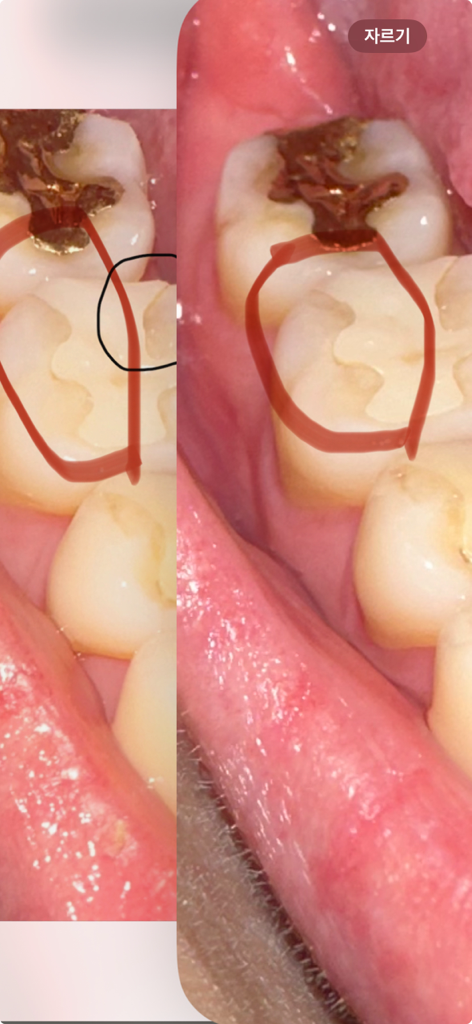

저기 빨간 동그라미 부분 왼쪽이 치료받기 전이고 오른쪽이 치료받은 후 입니다 제가 말한쪽이 아닌데 다른쪽을 다듬어줘버려서 멀쩡했던 부분 마저 저렇게 됐습니다.. 괜찮은걸까요? 문제될게 있을까요? ㅠㅠ

현재 사진상으로는 크게 문제가 되어 보이지는 않습니다. 하지만 현재 이물감이나 시리거나 통증 및 불편감이 나타나는 경우치과를 방문하여 진료를 받길 권합니다.